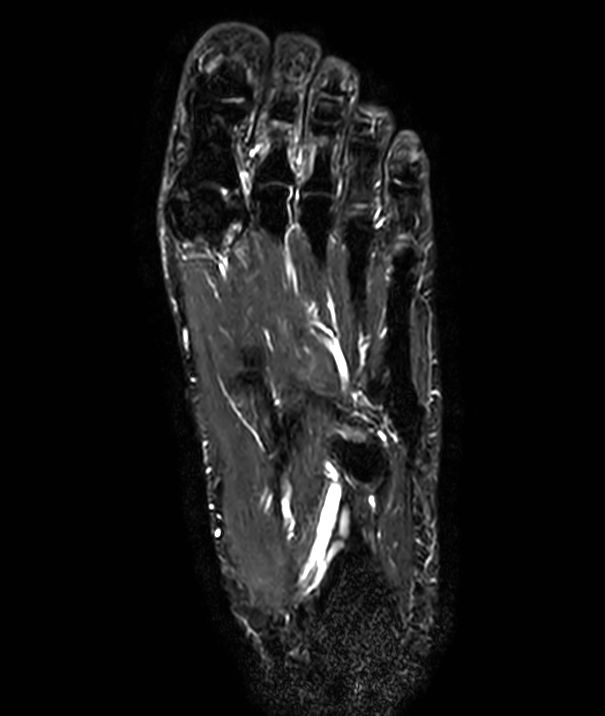

Coronal STIR TSE